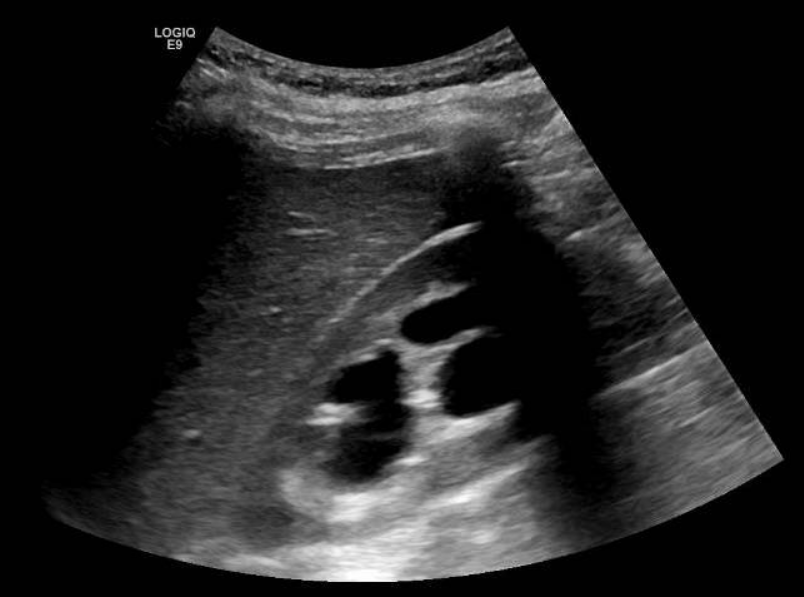

Se solicita ecografía abdominal donde se observa el riñón derecho de tamaño normal, con adelgazamiento parenquimatoso difuso secundario a ureterohidronefrosis severa que se extiende hasta la unión vesicoureteral, donde se visualiza una lesión anecoica intravesical, en relación con el ureterocele ya conocido, que condiciona el cuadro obstructivo.